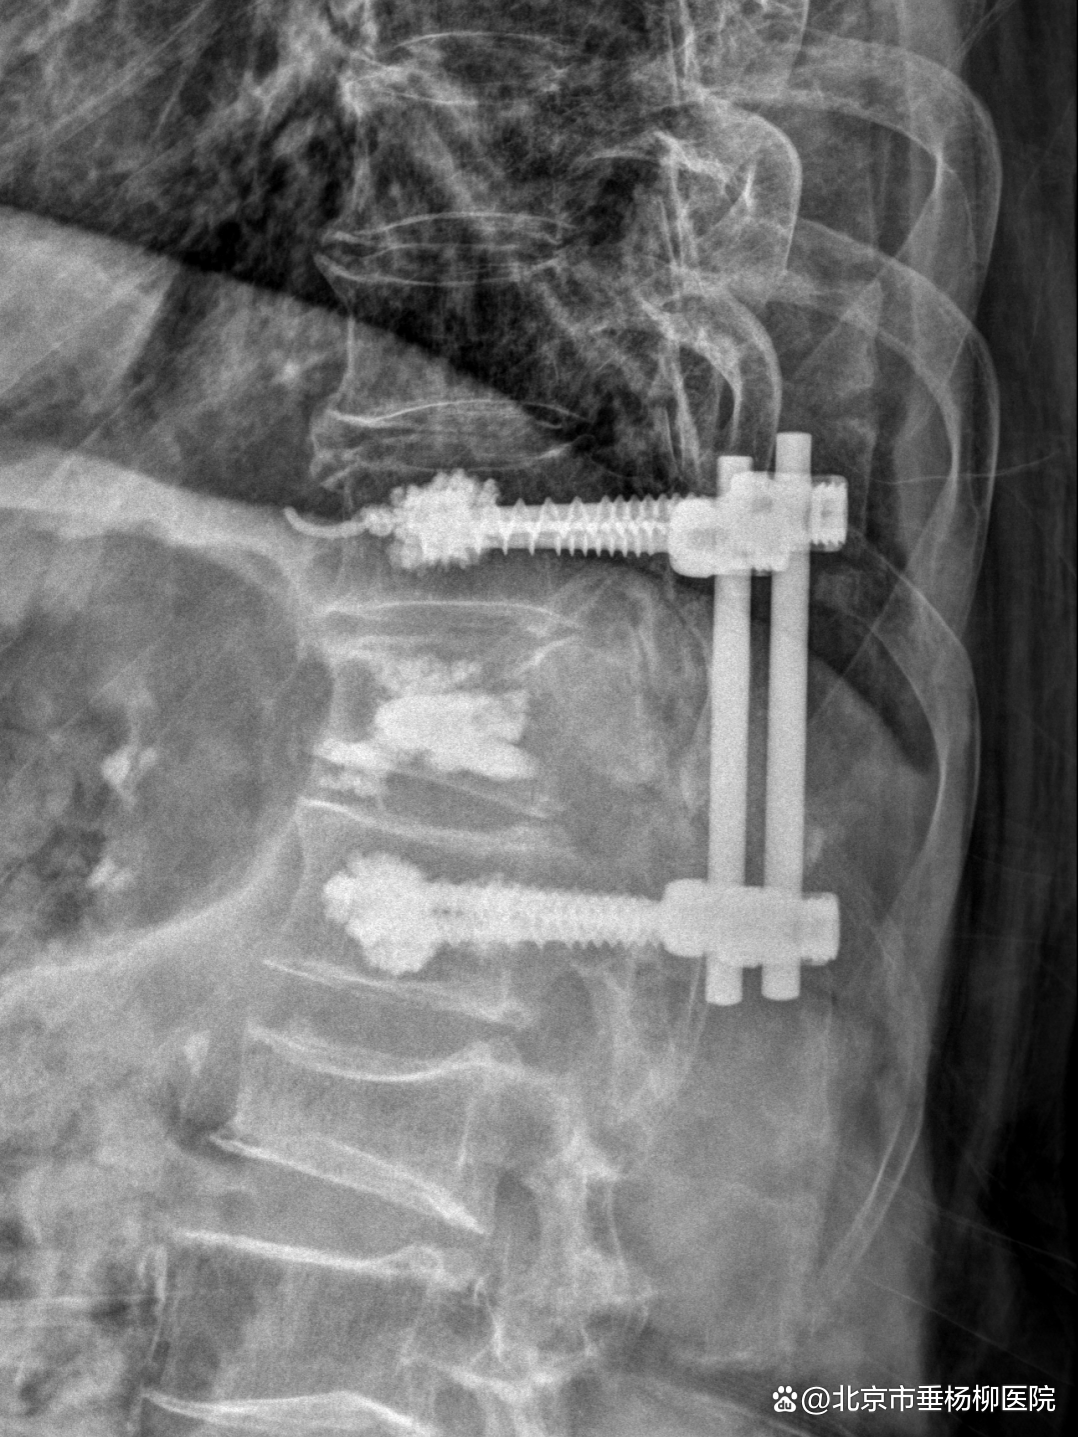

手术当日,姜树东会同脊柱外科(骨四科)主治医师梁得华在全麻下为患者进行后路胸椎椎板切除椎管减压、T12椎体强化术、T11、L1椎弓根钉内固定术、植骨融合术。手术过程顺利。术后患者恢复良好,腰背部显著缓解,在支具保护下可以进行常规活动。患者在术后1周顺利出院,后续接受抗肿瘤相关治疗。

▲术后